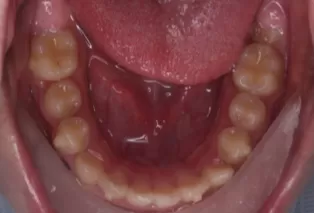

Intraoral photos